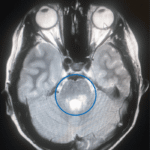

My story begins in childhood, when life changed in a way none of us expected. I was six when I was diagnosed with a brain tumour, and although the doctors couldn’t remove it because of where it was positioned, they operated to relieve pressure in my head caused by hydrocephalus. Years later, when I was eleven, the tumour began to grow again. I faced a biopsy that went deep into my brain and received a rare diagnosis – a tanycytic ependymoma. Treatment meant chemotherapy and radiotherapy, months in hospital, and more time away from school than in it.